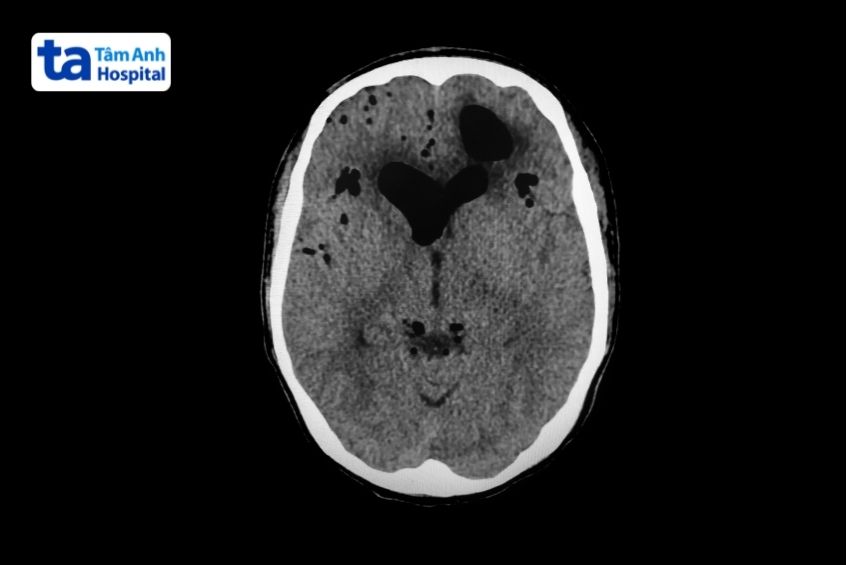

4. Hình ảnh xuất huyết khoang dưới nhện

Xuất huyết khoang dưới nhện thể hiện bằng vùng tăng tỷ trọng nằm ở các bể nền, rãnh cuộn não, rãnh Sylvius, rãnh liên bán cầu.

Ảnh chụp CT nhận diện xuất huyết khoang dưới nhện